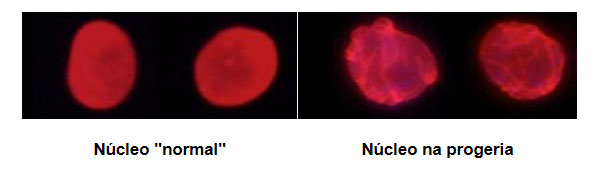

Na progeria o sítio de reconhecimento da enzima que requer a clivagem da prelamina A a lâmina A está mutado, não ocorrendo clivagem do grupo farnesil, formando assim uma proteína anormal denominada de progerina, uma forma truncada da prelamina A. A progerina é tóxica para a célula, acumula-se nas células causando defeitos moleculares progressivos, incluindo alterações do formato nuclear, desorganização da cromatina, danos no DNA e atraso na proliferação celular (Figura 2).

Devido à ausência de produção de lâmina A, a lâmina nuclear é incapaz de fornecer o suporte estrutural adequado ao invólucro nuclear, assumindo uma forma anormal. Uma vez que o apoio que a lâmina nuclear proporciona normalmente é necessário para a organização da cromatina durante a mitose, o enfraquecimento da lâmina nuclear limita a capacidade da célula se dividir. Esta alteração parece desestabilizar o núcleo das células, sendo particularmente nociva para os tecidos sujeitos a forças físicas como os cardiovasculares e os musculares ligados ao esqueleto. A mutação do gene causa uma forma alterada tornando as células instáveis e danifica o núcleo, impedindo a regeneração dos tecidos e provocando a morte prematura das células.

Figura 2 – Lâmina A (marcada a vermelho) em amostras de células controlo (saudáveis) e em células associadas a progeria.